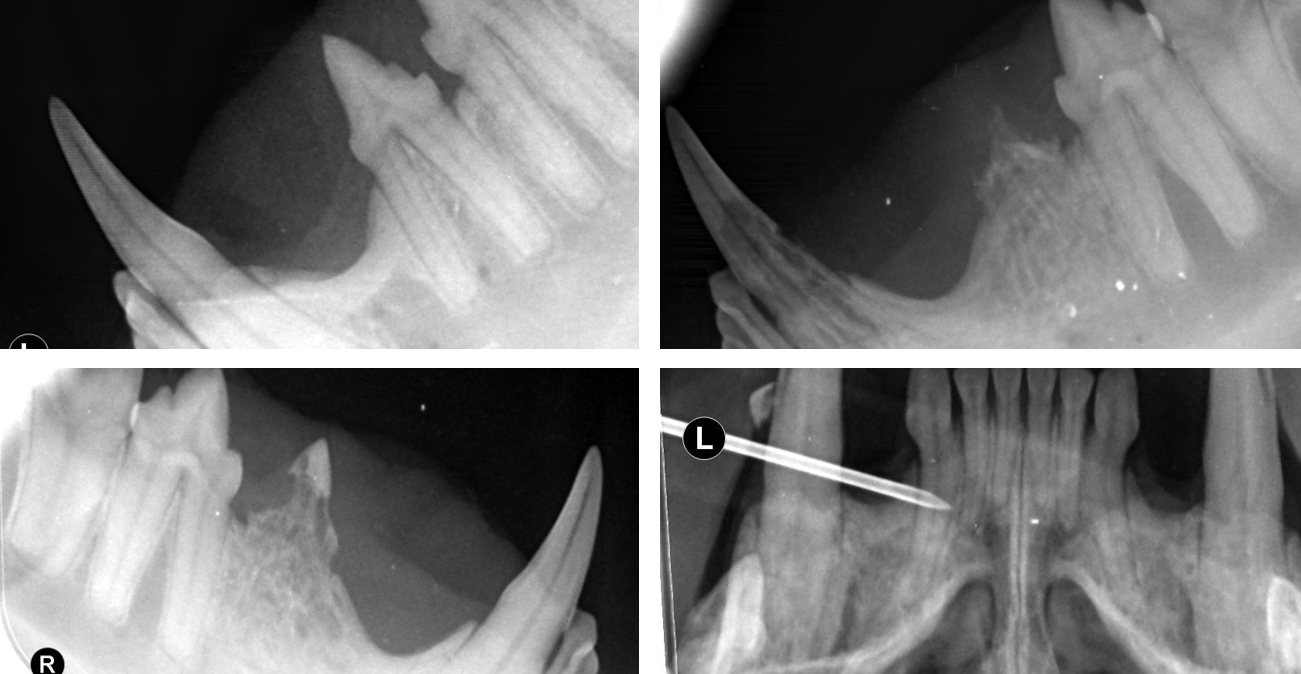

Das Dentalröntgen